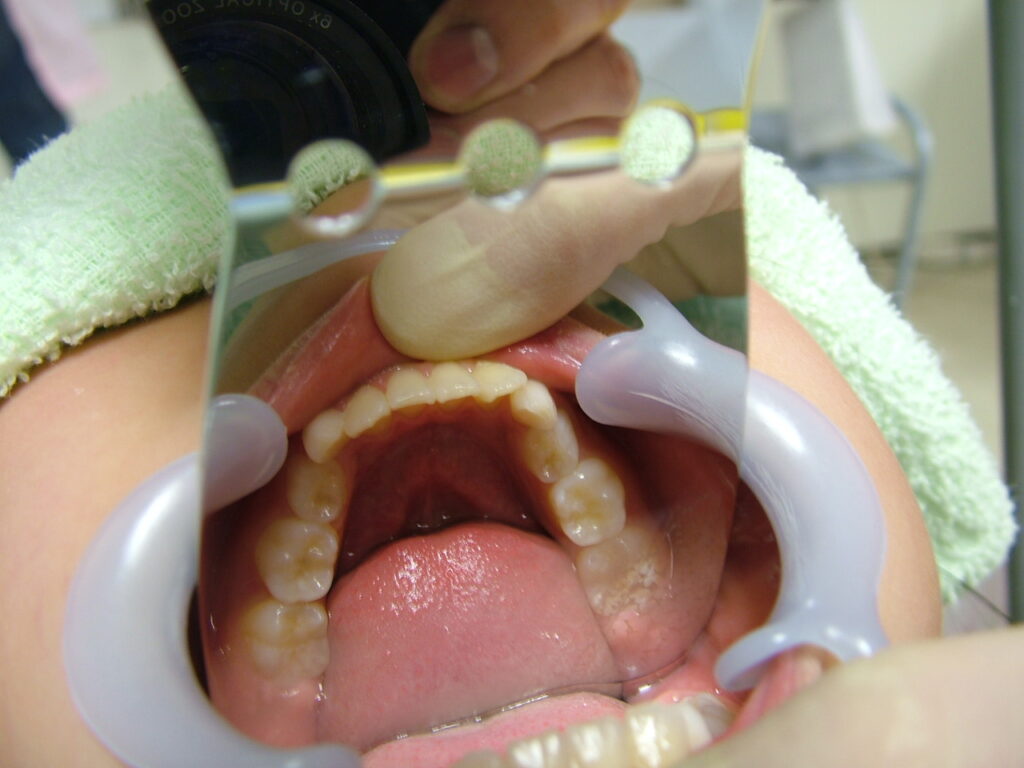

治療前

概要

- 初診:2016年、9歳女児

- 主訴:出っ歯と歯の隙間がきになる。

- 診断:2級過蓋咬合、上下永久歯(犬歯)萌出スペース不足

- 治療方針:非抜歯で行う。虫歯予防(フッ素)、歯磨き指導、上下拡大床→咬合関係改善のツインブロック(2級→1級関係へ)→マウスピース矯正→下親知らずの抜歯、保定→メンテナンス